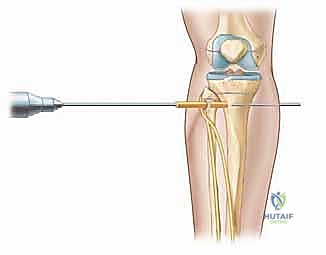

1. القطع العظمي القشري (Corticotomy): يقوم الجراح بقطع الطبقة الخارجية الصلبة للعظم مع الحفاظ التام على السمحاق (الغشاء المغلف للعظم) ونخاع العظم الداخلي، حيث تتركز الخلايا الجذعية والتروية الدموية.

2. يوم الجراحة: الدقة المتناهية

تحت التخدير المناسب، يقوم الدكتور هطيف بتركيب الجهاز (سواء الحلقات أو السكة الجانبية) بدقة بالغة مع مراعاة مسار الأعصاب والأوعية الدموية (وهنا تبرز أهمية خبرته في الجراحة الميكروسكوبية). بعد التثبيت، يتم إجراء القطع العظمي (Corticotomy) من خلال شق جراحي صغير جداً للحفاظ على التروية الدموية الحيوية.